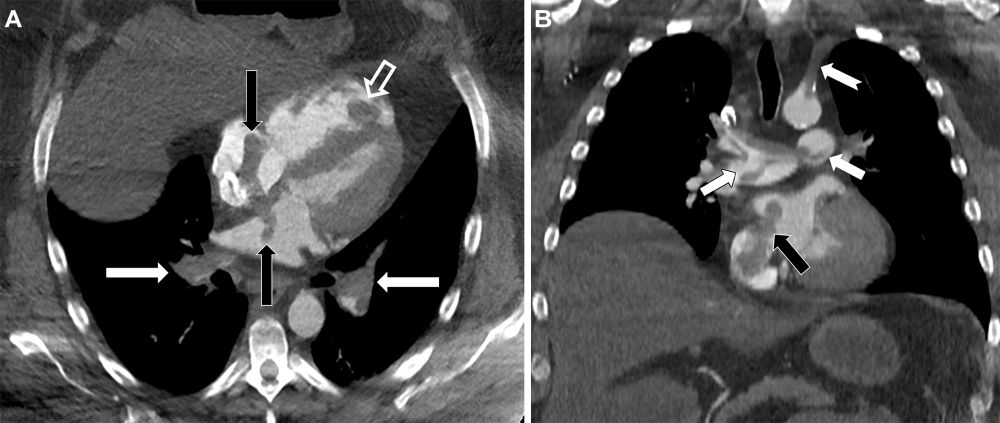

When clots take a detour! CT pulmonary angiography revealed multiple emboli, rt heart strain & thrombus sneaking through an undiagnosed ASD, causing paradoxical embolism w/ clot-in-transit 🫀

#Radiology

pubs.rsna.org/doi/10.1148/...

Paradoxical Embolism with Clot-in-Transit in Atrial Septal Defect | Radiology